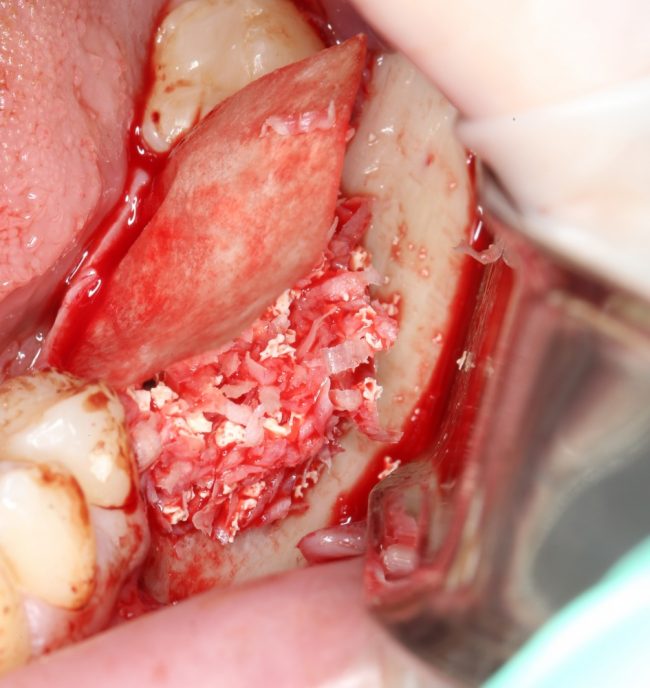

И наоборот, такой же по объему дефект, но не имеющий двух или трех стенок, «чистым» биоматериалом, практически, не вытянуть, поэтому мы должны (нет, обязаны!) добавлять в ксенографт аутокостную стружку:

что, как я уже писал, увеличивает предел роста:

И дает возможность получить нормальный результат остеопластики почти в любом объеме.